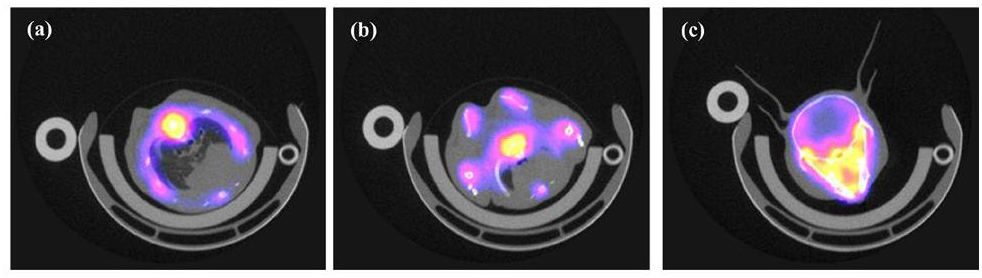

The mouse bone structure can be distinctly identified with 18F labeling, as illustrated in Fig. 19(a-c), which displays PET/CT images of three slices that depict the mouse rib, arm, and head. PET images were manually registered and superimposed with CT images. The results demonstrate a high level of consistency between the PET images and the bone images obtained via CT.